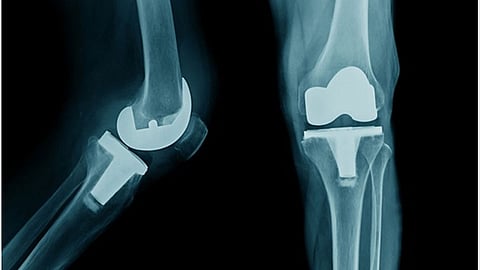

पुणे - दोन्ही गुडघा बदलीच्या शस्त्रक्रियेनंतर (Knee Surgery) ६३ वर्षांच्या महिलेने (Women) ३,५०० किलोमीटर नर्मदा परिक्रमा पायी (Walking) पूर्ण केली. पुण्यातील साईश्री हॉस्पिटलमध्ये त्यांच्यावर शस्त्रक्रिया झाली होती. (63 Year Old Woman Walks 3500 Kilometers after Knee Replacement)

सुलभा कुलकर्णी या २००९ पासून गुडघेदुखीने त्रस्त होत्या. दैनंदिन जीवनातील कामे करताना त्यांना त्रास होत होता. डॉक्टरांनी त्यांना गुडघाबदलीची शस्त्रक्रिया सांगितली होती; परंतु सरकारी कर्मचारी असल्याने आणि घरगुती कामामुळे त्या शस्त्रक्रिया करण्यासाठी मानसिकदृष्ट्या तयार नव्हत्या. २०१५ मध्ये जेव्हा त्या सेवानिवृत्त झाल्या, तेव्हा त्यांना गुडघेदुखीचा त्रास जाणवू लागला. म्हणून त्यांनी गुडघाबदलीची शस्त्रक्रिया करण्याचा निर्णय घेतला. साईश्री हॉस्पिटल येथे रोबोटिक जॉइंट रिप्लेसमेंट सर्जन डॉ. नीरज आडकर यांच्या नेतृत्वात कुलकर्णी यांच्यावर शस्त्रक्रिया केली.